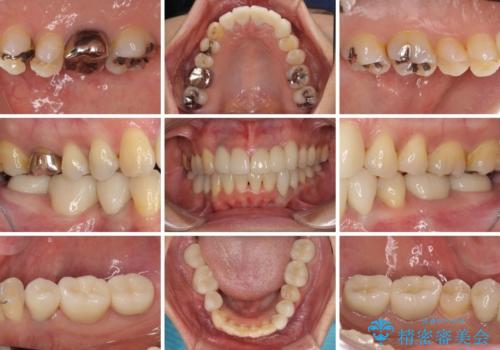

- 非対称な前歯や奥歯の目立つ銀歯を気にして来院された患者様です。

左上前から2番目の歯は、以前裏側に位置していたことから抜歯をされていましたが、前歯の非対称が長年気になっているとのことでした。

矯正治療によって前歯にスペースを作り、左右対称となるようにオールセラミッククラウンにて補綴治療を行うとしました。

他にも奥歯の咬み合わせに問題があったので、全顎的な矯正治療を行い、前歯以外にも口を開けたときに目立つ奥の銀歯をセラミッククラウンにて補綴治療を行うこととしました。